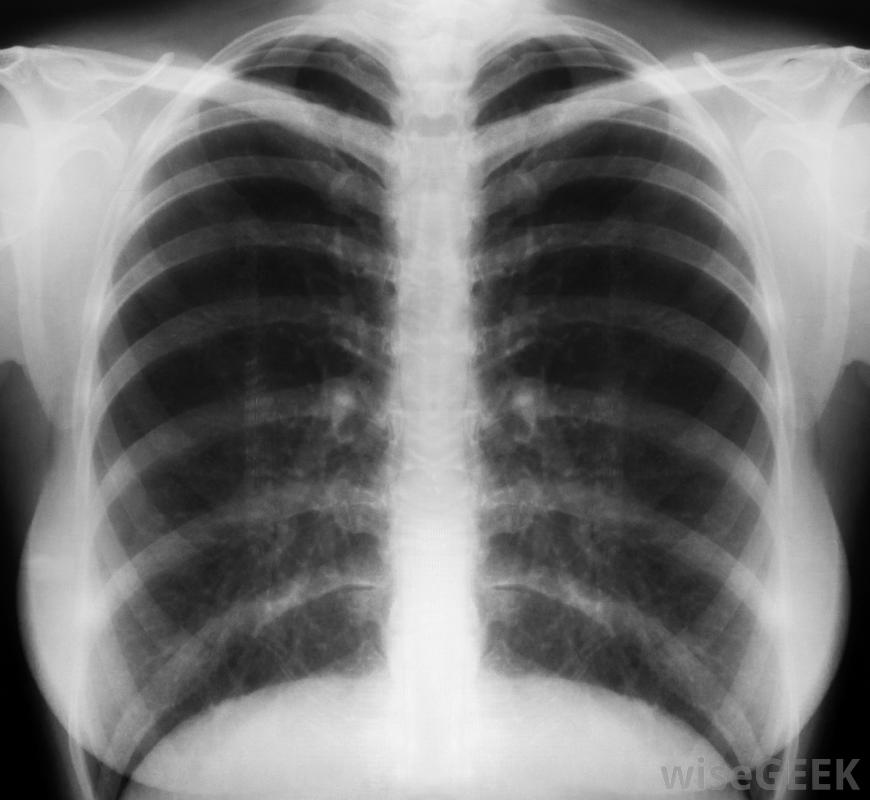

肋軟骨炎的治療主要包括消炎藥和止痛藥,其中許多不用處方就可以買到。通常,這種情況下的疼痛會在沒有額外治療的情況下消失,因此,休息有時是唯一的處方。一些醫生也可能會開一種肌肉松弛劑來治療肋軟骨炎,或者建議只要有疼痛就在胸前敷上一塊加熱墊。肋軟骨炎就是這樣肋骨和胸骨之間軟骨的炎癥。肋骨軟骨炎的治療方式也可能取決于病因肋軟骨關節炎位于胸腔的肋軟骨關節。雖然這不是一種嚴重或危及生命的疾病,但它非常痛苦,醫生也不確定是什么原因引起的,盡管人們經常懷疑某種形式的關節炎。在某些情況下,肋軟骨炎可能是由上呼吸道感染或損傷引起的,如果癥狀是由這兩種情況引起的,治療肋軟骨炎也包括治療感染或損傷如果懷疑肺部感染或其他損傷,可要求進行胸部x光檢查大多數醫生建議服用布洛芬,這是一種可以在柜臺購買的消炎止痛藥。專家建議,這只應該作為一種治療手段,在進行檢查以確定肋骨軟骨炎是否是導致胸痛的原因后,健康專家不建議嘗試自我診斷這種疼痛,也不建議在進行徹底檢查之前進行特定的肋軟骨炎治療在決定肋骨軟骨炎的治療方法之前,醫生會檢查胸部,同時按壓肋軟骨關節周圍。如果患者在檢查時報告該區域疼痛或酸痛,醫生通常會診斷這種疼痛是由這種情況引起的。通常只有在檢查后才建議對這種情況進行各種治療。如果懷疑有其他疾病,如肺部感染,或者,如果最近有明顯的損傷,醫生可能會提供進一步的檢查,其中可能包括胸部x光片。當疼痛歸因于這些情況之一時,肋軟骨炎的治療也包括治療潛在的原因。在某些情況下,醫生會建議對胸部進行熱敷或冷敷以減輕疼痛。在大多數情況下,肋軟骨炎的治療非常少。許多人發現休息幾天后疼痛和炎癥會自然消失對于一些人來說,癥狀只出現在劇烈運動期間,并在停止運動后很快消退。在這些情況下,肋軟骨炎止痛藥治療可能會幫助那些盡管疼痛仍想繼續鍛煉的人。